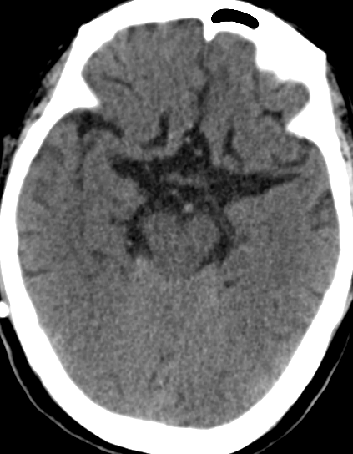

2015-3-31

脑压100

2015-4-1 MRI

诊断

脑膜癌?

特发性肥厚性硬脊膜炎?

进展性特发性肥厚性硬脊膜炎